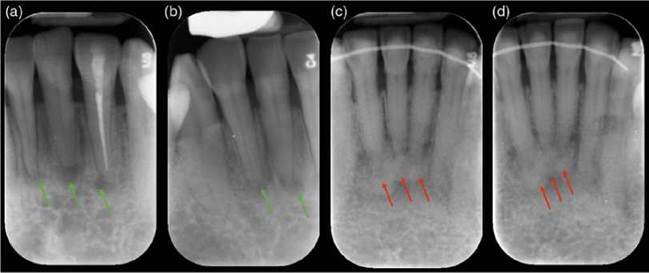

Figure 6.22 Periapical cemental dysplasia. (a, b) Early stage: well-defined radiolucencies (green arrows) associated with the all the lower incisor teeth. The teeth test vital, but tooth 32 was misdiagnosed to have apical periodontitis and was root treated. (c, d) Intermediate stage: periapical radiographs of the lower incisor region reveals a poorly defined radiolucency with patchy radiopaque inclusions (red arrows) associated with vital lower incisor teeth.